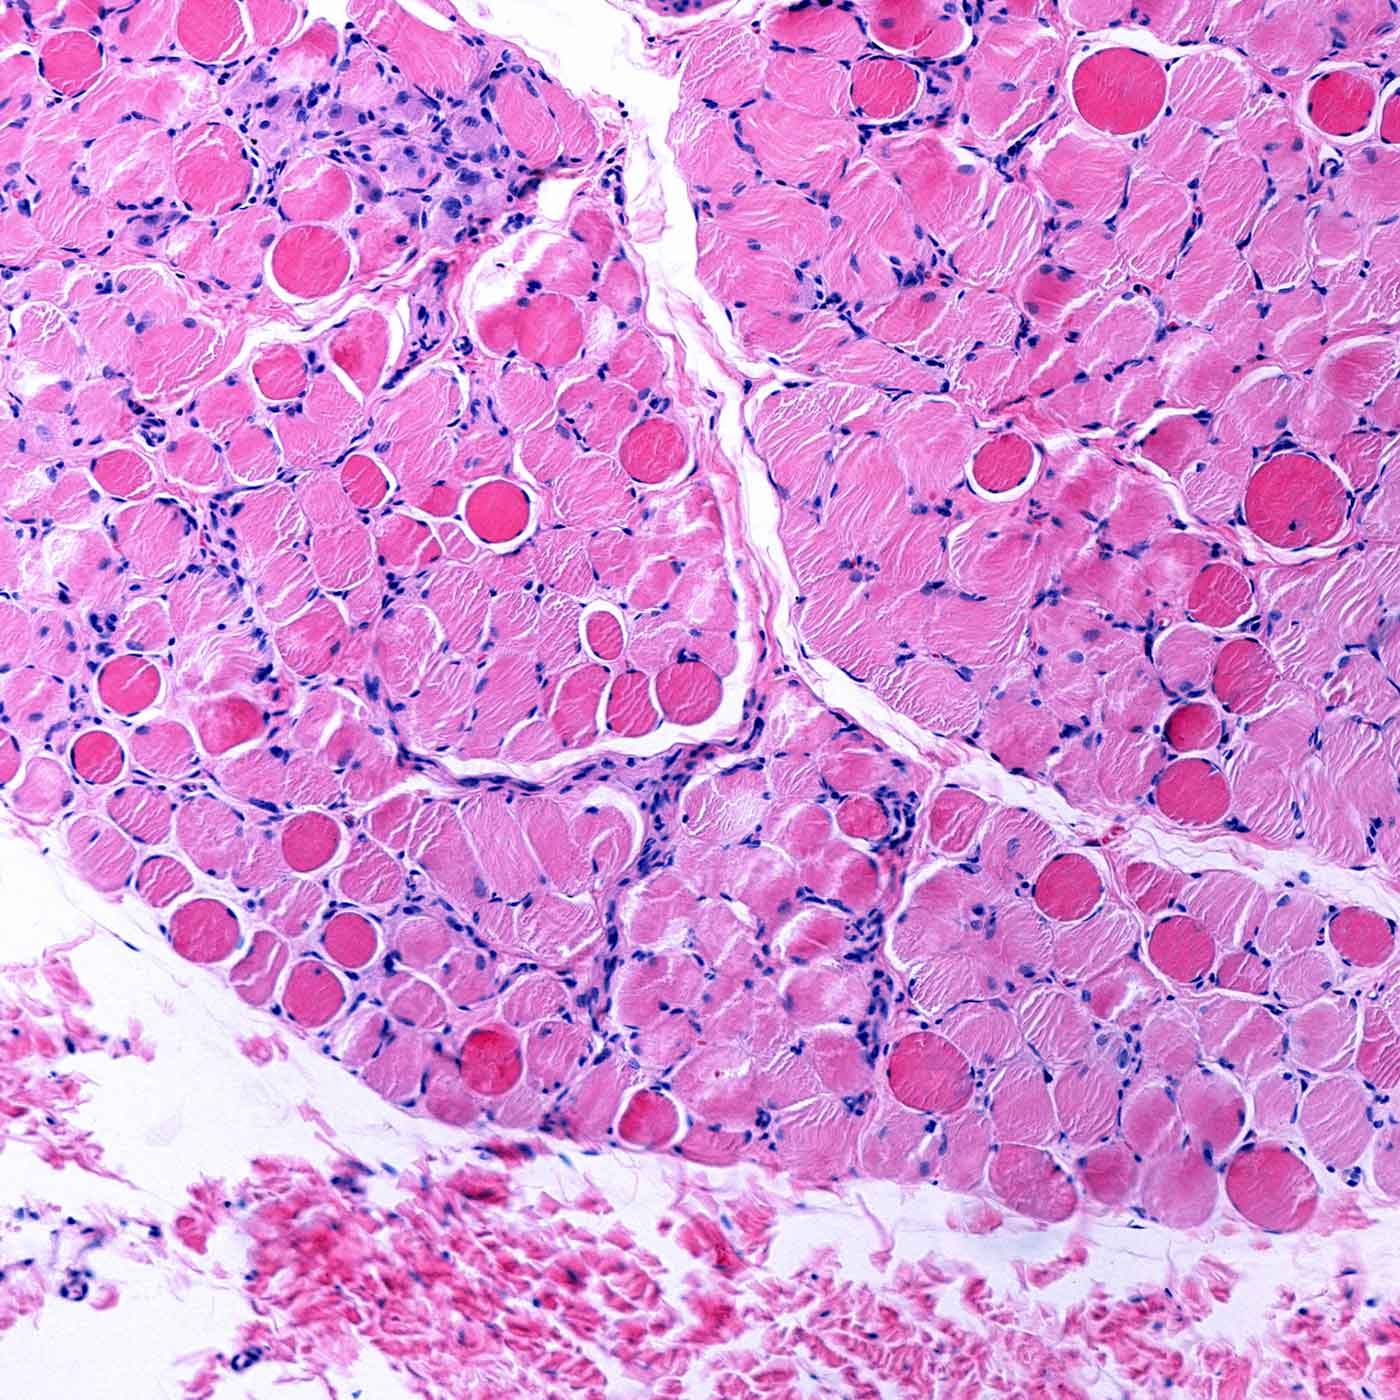

While there are more treatments now than ever before for neuromuscular diseases like muscular dystrophy, patients who have very specific gene mutations associated with these diseases have few options. Dr. Elizabeth McNally says a discovery in her lab could lead to a new therapy for muscular dystrophy, including its rare forms.